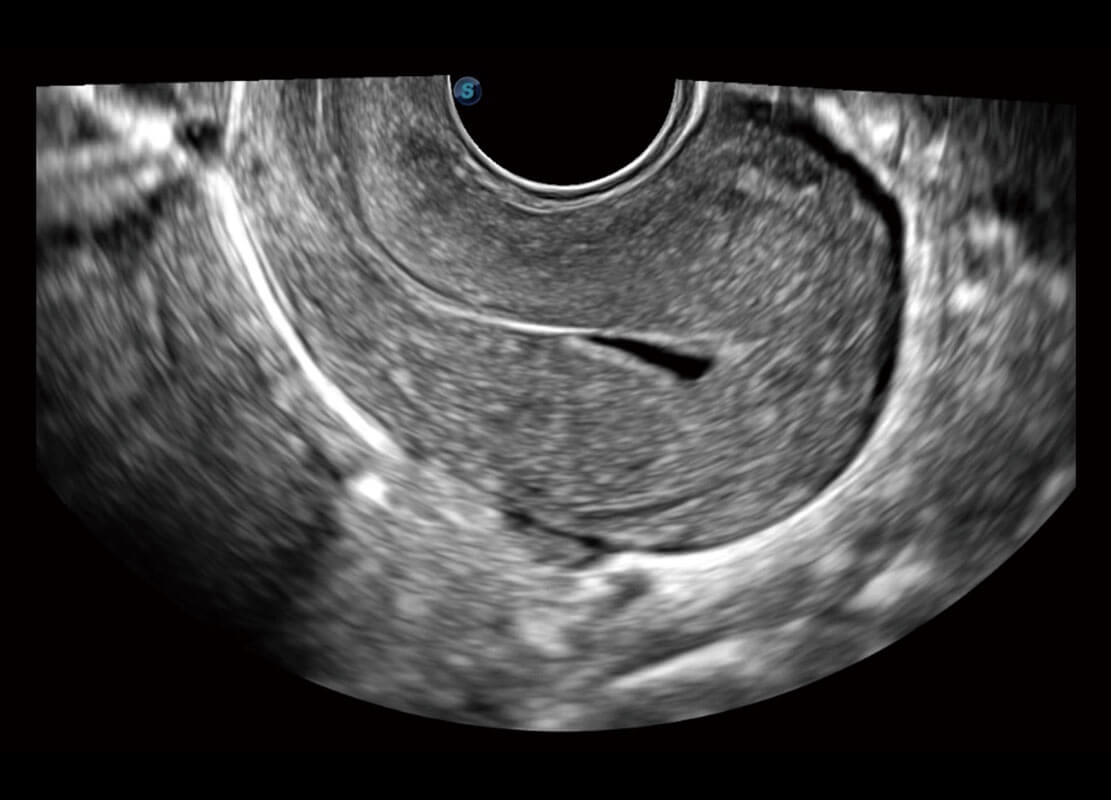

生殖健康

P60卓越的图像质量搭载专科探头,在妇科基础疾病的诊断、卵泡生长的监测、输卵管通畅情况的判别等方面为您提供全面的生殖应用方案。

• 腔内妇科-宫腔分离

• 腔内妇科-卵巢

• 腔内三维-宫内节育器

• 腔内三维-光影成像